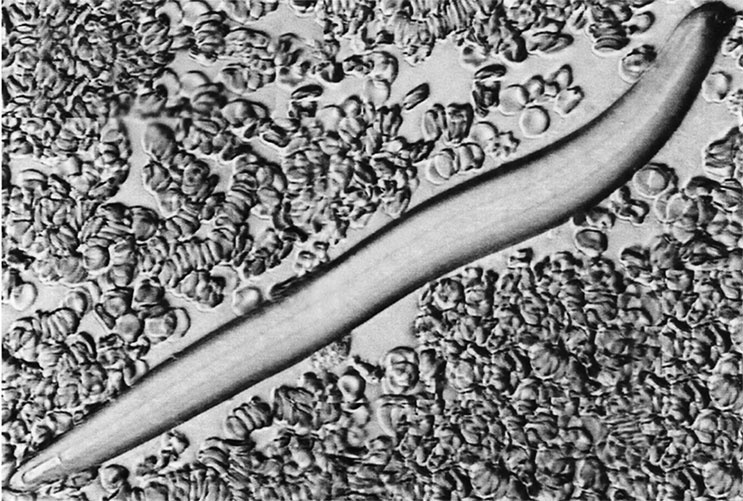

Глистов и личинок псевдодиагносты находят практически у каждого пациента. Что мы видим на фото на самом деле? Продолговатый артефакт, абсолютно не похожий на яйцо какого-либо из описанных на сегодня гельминтов. Другими словами, мусор, попавший в рассматриваемую каплю крови, – осевший из воздуха, оставшийся на плохо обработанном предметном стекле или упавший с головы оператора. Последнее, кстати, возможно из-за нарушения требований к работе в клинической лаборатории. На фото в Интернете, как и в реальной практике, операторы зачастую не пользуются ни перчатками, ни шапочками, ни масками. Да и помещения для диагностики оставляют желать лучшего в смысле чистоты. Там много чего в воздухе летает. А как же тогда получаются вот такие картинки из атласа? ![]() Личинка паразита Элементарно. Здесь действительно изображен круглый червь, хорошо видны и ротовое отверстие, и просвечивающая кишка. Однако его поместили в образец крови позже. Доказать это очень просто: мы видим эритроциты, окружающие «личинку». Их диаметр – около 7,5 мкм. Самая широкая часть гельминта соответствует примерно трем эритроцитам с фото, то есть его максимальный диаметр – 22–23 мкм. И он не поместится ни в один капилляр (их диаметр, напомню, 5 мкм, максимум 10). Через прокол в пальце такой монстр выберется наружу, только если сзади его будут подталкивать сородичи, выкрикивая при этом: «Давай, ты сможешь, мы в тебя верим!» Так что в данном случае мы имеем дело с обычным постановочным, срежиссированным фото. Другими словами – с «фейком». С таким же успехом туда можно положить головную вошь и заявить, что она прогрызла кожу головы и с током крови добралась до подушечки пальца. Я даже термин могу под это с ходу придумать – педикулемия («педикулюс» – латинское название рода вшей, а «-емия» означает наличие чего-нибудь в крови). Трихомонада – любимый паразит шарлатанов. На ней построено несколько альтернативных гипотез развития болезней, в частности рака. И само собой, придумано много несуществующих характеристик этого микроорганизма. Например, во всех современных руководствах по микробиологии указано, что трихомонада не способна образовывать защитную форму – цисту, именно поэтому очень быстро гибнет во внешней среде [59]. Это легко подтверждается простейшим лабораторным экспериментом. Тем не менее адепты альтернативных направлений заявляют, что трихомонада может образовывать цисты, правда, подтверждений своим словам никогда не приводят, а ссылаются на другие книги и брошюры с точно таким же голословным утверждением. Зачастую мы имеем дело с обычным постановочным фото. С таким же успехом туда можно положить головную вошь и заявить, что она прогрызла кожу головы и с током крови добралась до подушечки пальца. В тех же ненаучных источниках сообщается, что трихомонада, например ее влагалищная разновидность, умеет проникать в кровоток [60]. Опять же, без ссылок на исследования, тем более опубликованные в рецензируемых журналах. Подобные книги вообще не жалуют такую вещь, как библиография. Это нам – медицинским журналистам и нашим коллегам-ученым – приходится подтверждать каждое свое высказывание, а шарлатанам принято верить на слово. И что характерно, им почему-то верят. ![]() Трихомонада Но вернемся к трихомонаде, путешествующей по крови. Нормальной микробиологии такая разновидность паразита неизвестна. Зато известно, что влагалищная трихомонада – овальный микроорганизм размером 7×9 мкм (чуть больше эритроцита) с пятью хорошо заметными жгутиками с одного из полюсов. И как она выглядит, тоже не секрет. Вот, скажем, фото микропрепарата из общедоступной библиотеки американского Центра по контролю и профилактике заболеваний (CDC) в Атланте [61]. Так что на иллюстрации из атласа гемосканирования однозначно не трихомонада. А кто тогда? Скорее не кто, а что. Эритроциты. Точно такие же, как и в других областях фотографии. А почему они такой странной формы? ![]() Трихомонада-CDC Все просто: капля крови – образование объемное, клетки в ней располагаются не в один ряд и не только анфас. Эритроциты тоже трехмерны, по форме напоминают сплюснутый в центре оладушек. Свет, идущий через эритроцит в объектив микроскопа, лучше проходит через его тонкие места и хуже – через утолщения. В результате мы и наблюдаем эритроциты в виде кружков со светлым центром. Например, вот эта фотография в атласе подписана как «Норма». ![]() Норма Но если красные клетки крови повернуты к наблюдателю боком или развернуты под любым другим углом, то и выглядеть они будут не как кругляши. Один из таких вариантов шарлатаны и выдают за трихомонаду. А вот и самый интересный экземпляр из моей коллекции микропрепаратов, собранной по различным источникам, посвященным гемосканированию. ![]() Антенна-1 Впечатляюще выглядит, не правда ли? Если пациент увидит этакое страшилище в своей крови, он отдаст любые деньги, лишь бы от него избавиться. Собственно, на это и расчет. |